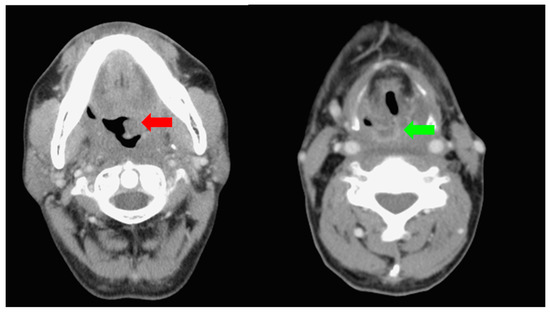

2. Case Presentation